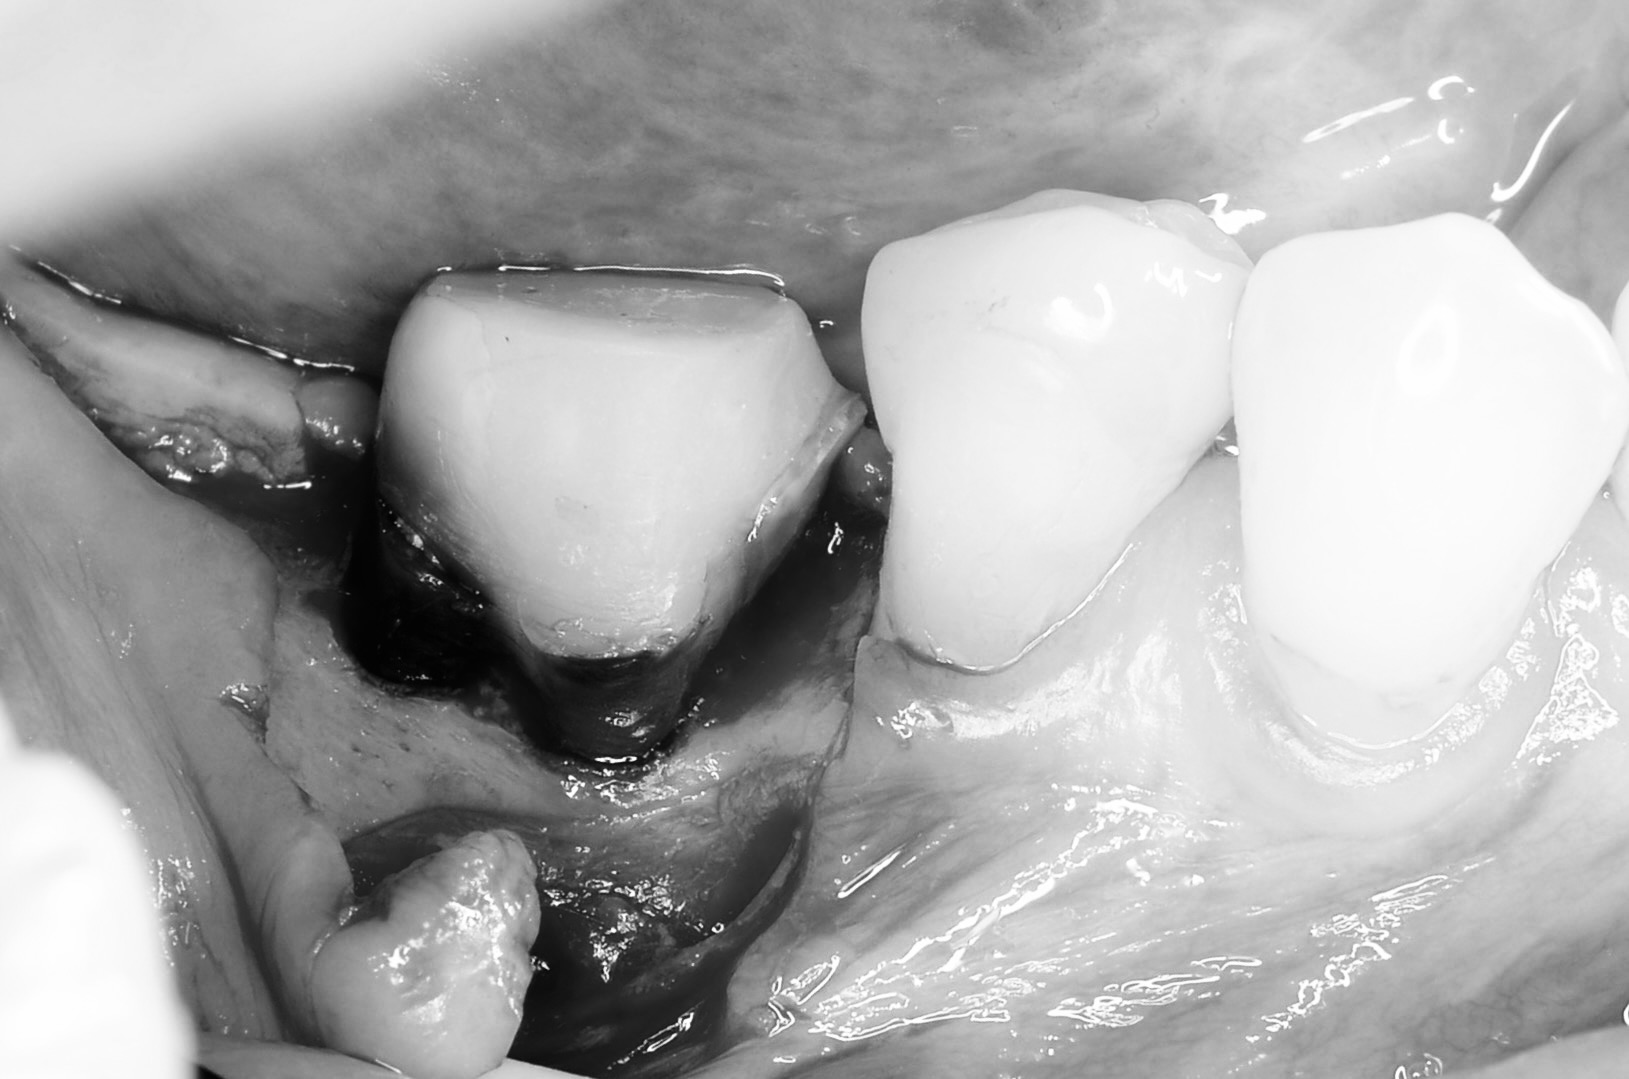

骨外科処置

隣在歯との骨の高さのバランスを見ながら歯槽骨を削り歯根を露出させます。 -